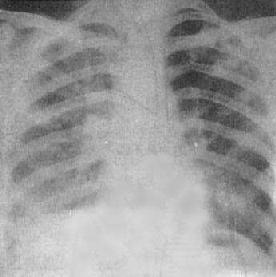

肺实变(右中叶大叶性肺炎)

图3-1-11 肺实变(右中叶大叶性肺炎)

相当于右肺中叶密度均匀增高,后前位上,上缘清楚,下缘模糊,

侧位上呈三角形致密影,尖端在肺门区